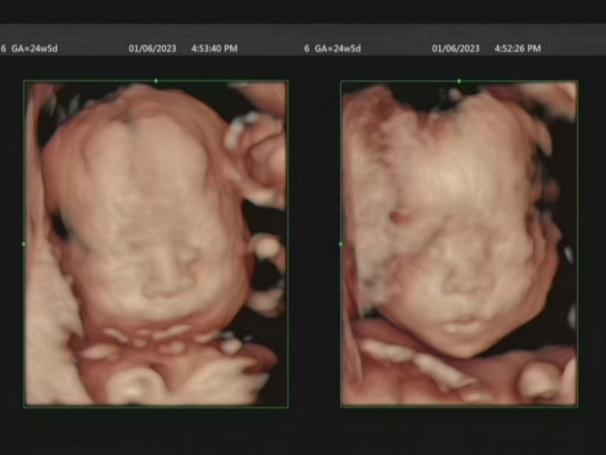

? 11月12日,從超聲科獲悉,該科為一過(guò)度肥胖孕婦成功完成四維系統(tǒng)超聲檢查,得知胎兒發(fā)育良好,該孕婦十分感動(dòng)。

該孕婦石女士,懷孕24周,因過(guò)度肥胖、腹壁脂肪層過(guò)厚、檢查難度大,輾轉(zhuǎn)多家醫(yī)院篩查均未成功。當(dāng)日,經(jīng)彩超室李莉醫(yī)生評(píng)估后,決定為其做胎兒系統(tǒng)超聲篩查。鑒于石女士自身?xiàng)l件因素,檢查過(guò)程并不順利。由于超聲波通過(guò)厚厚的腹壁脂肪后衰減嚴(yán)重,胎兒圖像質(zhì)量較差,給檢查診斷帶來(lái)不小的困難。李莉指導(dǎo)石女士積極配合,通過(guò)更換不同的體位,一邊仔細(xì)檢查,一邊耐心地從醫(yī)學(xué)角度認(rèn)真分析,為石女士答疑解惑。經(jīng)過(guò)1個(gè)多小時(shí)的系統(tǒng)操作,終于成功完成檢查,胎兒各方面生長(zhǎng)發(fā)育良好。石女士非常高興,對(duì)李莉的專(zhuān)業(yè)技術(shù)和服務(wù)態(tài)度連連點(diǎn)贊。

四維彩超可以為胎兒生成直觀立體的動(dòng)態(tài)圖像,不存在射線、光波和電磁波等輻射,對(duì)人體健康沒(méi)有影響,可以讓準(zhǔn)媽媽看到宮內(nèi)寶寶的一舉一動(dòng),感受到寶寶的笑容相貌,為寶寶留下永久紀(jì)念。

胎兒四維彩超是孕中期一個(gè)重要的檢查,是排除胎兒畸形最合適的時(shí)間,檢查最佳時(shí)期是在懷孕22周至26周。因?yàn)檫@段時(shí)間是胎兒大腦快速發(fā)育的階段,也是胎兒各方面發(fā)育呈良好狀態(tài)的時(shí)候。寶寶的大小和羊水量也都適中,在宮內(nèi)還有較大的活動(dòng)空間,胎兒的骨骼回聲影響也比較小,做出來(lái)的圖像也比較清晰,可以及時(shí)發(fā)現(xiàn)胎兒是否存在畸形等問(wèn)題。